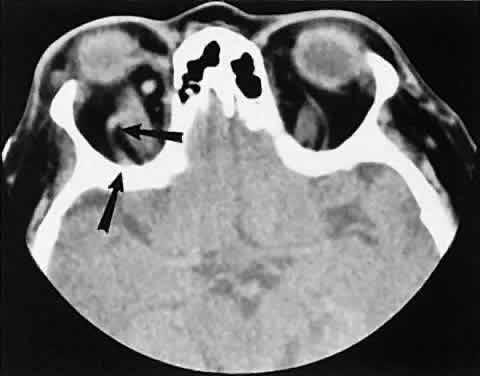

The muscle belly has a smooth contour with no edema of the adjacent orbital fat. We recently evaluated a patient with a referral diagnosis of Graves' orbitopathy. The patient was euthyroid but had severe orbital congestion typical of advanced Graves' orbitopathy. Imaging showed “dirty” orbital fat and lateral rectus muscle morphology that seemed atypical (Fig. 8). Biopsy specimen results showed a low-grade lymphoma. Hypertrophy of the medial rectus muscle can cause the medial wall to bow in toward the ethmoidal sinus from the chronic effects of pressure on the bone. The hypertrophied muscles also can give rise to a compressive optic neuropathy in the orbital apex as the enlarged muscles take their origin from the anulus of Zinn. Axial views of the apex show an apparent mass if the inferior rectus muscle is enlarged. It is imperative that additional views, sagittal or preferably coronal, be obtained to show the true nature of this apparent mass. Intracranial fat prolapse, seen by CT, may be another sign of optic neuropathy.44 An optic neuropathy also can be seen with relatively normal-sized EOM. An expanded fat compartment with optic nerve stretch has been associated with an optic neuropathy.45,46

Fig. 8. Low-grade lymphoma confined to orbit mistaken for Graves' ophthalmopathy in a 65-year-old man. A. On the axial view, orbital fat appears “dirty” with marked increase in soft tissue stranding. Muscles do not have a smooth appearance, lateral rectus muscles have lumpy appearance (arrow), and both lateral rectus muscles are disproportionately large for what typically is seen in Graves' orbitopathy. B. Coronal view also shows dirty orbital fat. Note left inferior rectus, which is small (arrowhead), and also is atypical in Graves' orbitopathy when there is enlargement of the other extraocular muscles.